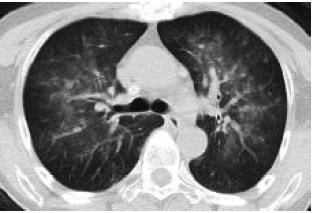

2.年轻女性,发热,气促,咳嗽,CT如下:

病灶也是略呈蝶羽征。

患者发热,咳嗽,明显呼吸困难,H1N1阳性。

重型甲流病毒性肺炎。